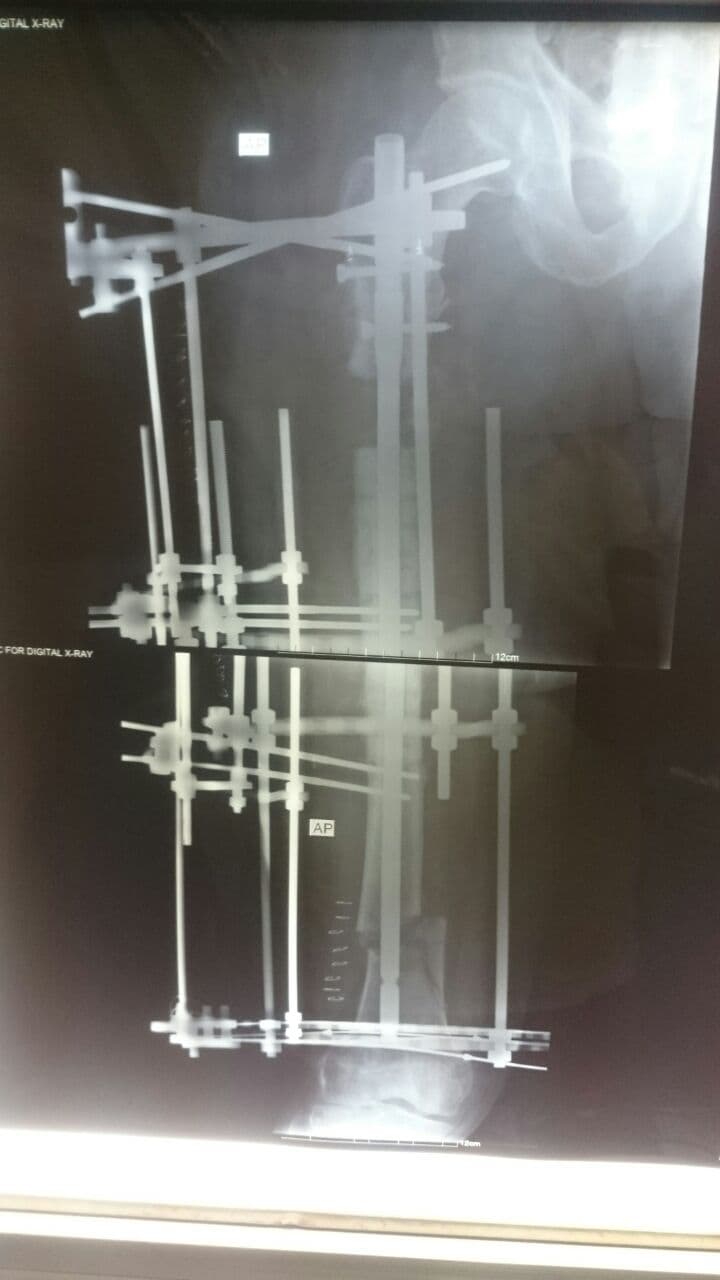

وقال إختصاصي جراحة العظام والكسور والمفاصل بالمستشفى الدكتور محمد سعد الحارس، في حديث صحافي، إن فريقنا الطبي نجح بعملية تثبيت كسر مع تطويل العظم لفخذ مريض يبلغ من العمر (70) عاما، مبيناً إن عملية التثبيت والتطويل اُجريت بإستخدام تقنية الإليزاروف.

وأوضح الحارس، إن المريض يعاني من فقدان عظمي أعلى عظم الفخذ يبلغ (7) سم مع التهاب عظمي نتيجة عملية سابقة، مؤكداً إستعادة المريض لعافيته عقب عمليته التي اجريناها في مستشفى الكفيل.